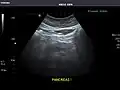

Abdominal Ultrasound (Full Exam)

STRUCTURED REPORT

(Technique: Transabdominal ultrasonography; Device: Toshiba Aplio XG)

Pancreas: Visualized portions unremarkable.

Pancreas -